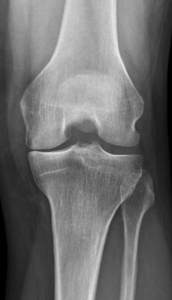

Le diagnostic repose sur un faisceau d’arguments cliniques (interrogatoire, examen physique) et sur l’imagerie (pincement de l’articulation, présence d’ostéophytes ou « becs » osseux). Lorsque ces signes sont présents, il n’est pas nécessaire d’effectuer d’autres examens à visée diagnostique que la radiographie standard.

Lorsque l’usure du genou atteint 2 ou 3 compartiments (gonarthrose tricompartimentale) (Fig.7)